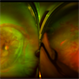

- retinopathy of prematurity, aggressive posterior retinopathy of prematurity (APROP)

- Premature baby referred for ROP evaluation. HALF ZONE 1 was only vascularised, Patient was given Inj Anti-Vegf follwed by ROP Laser after 1 week